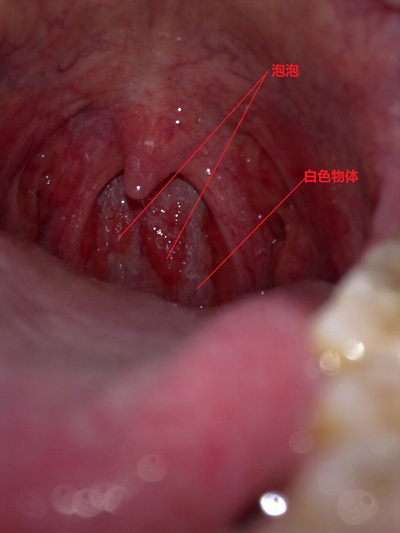

扁桃體結石

扁桃體結石

扁桃體結石

扁桃體結石

扁桃體結石

扁桃體結石

扁桃體結石

扁桃體結石

扁桃體結石

扁桃體結石

扁桃體結石

扁桃體結石

扁桃體結石

扁桃體結石

扁桃體結石

扁桃體結石

扁桃體結石

扁桃體結石

扁桃體結石

扁桃體結石